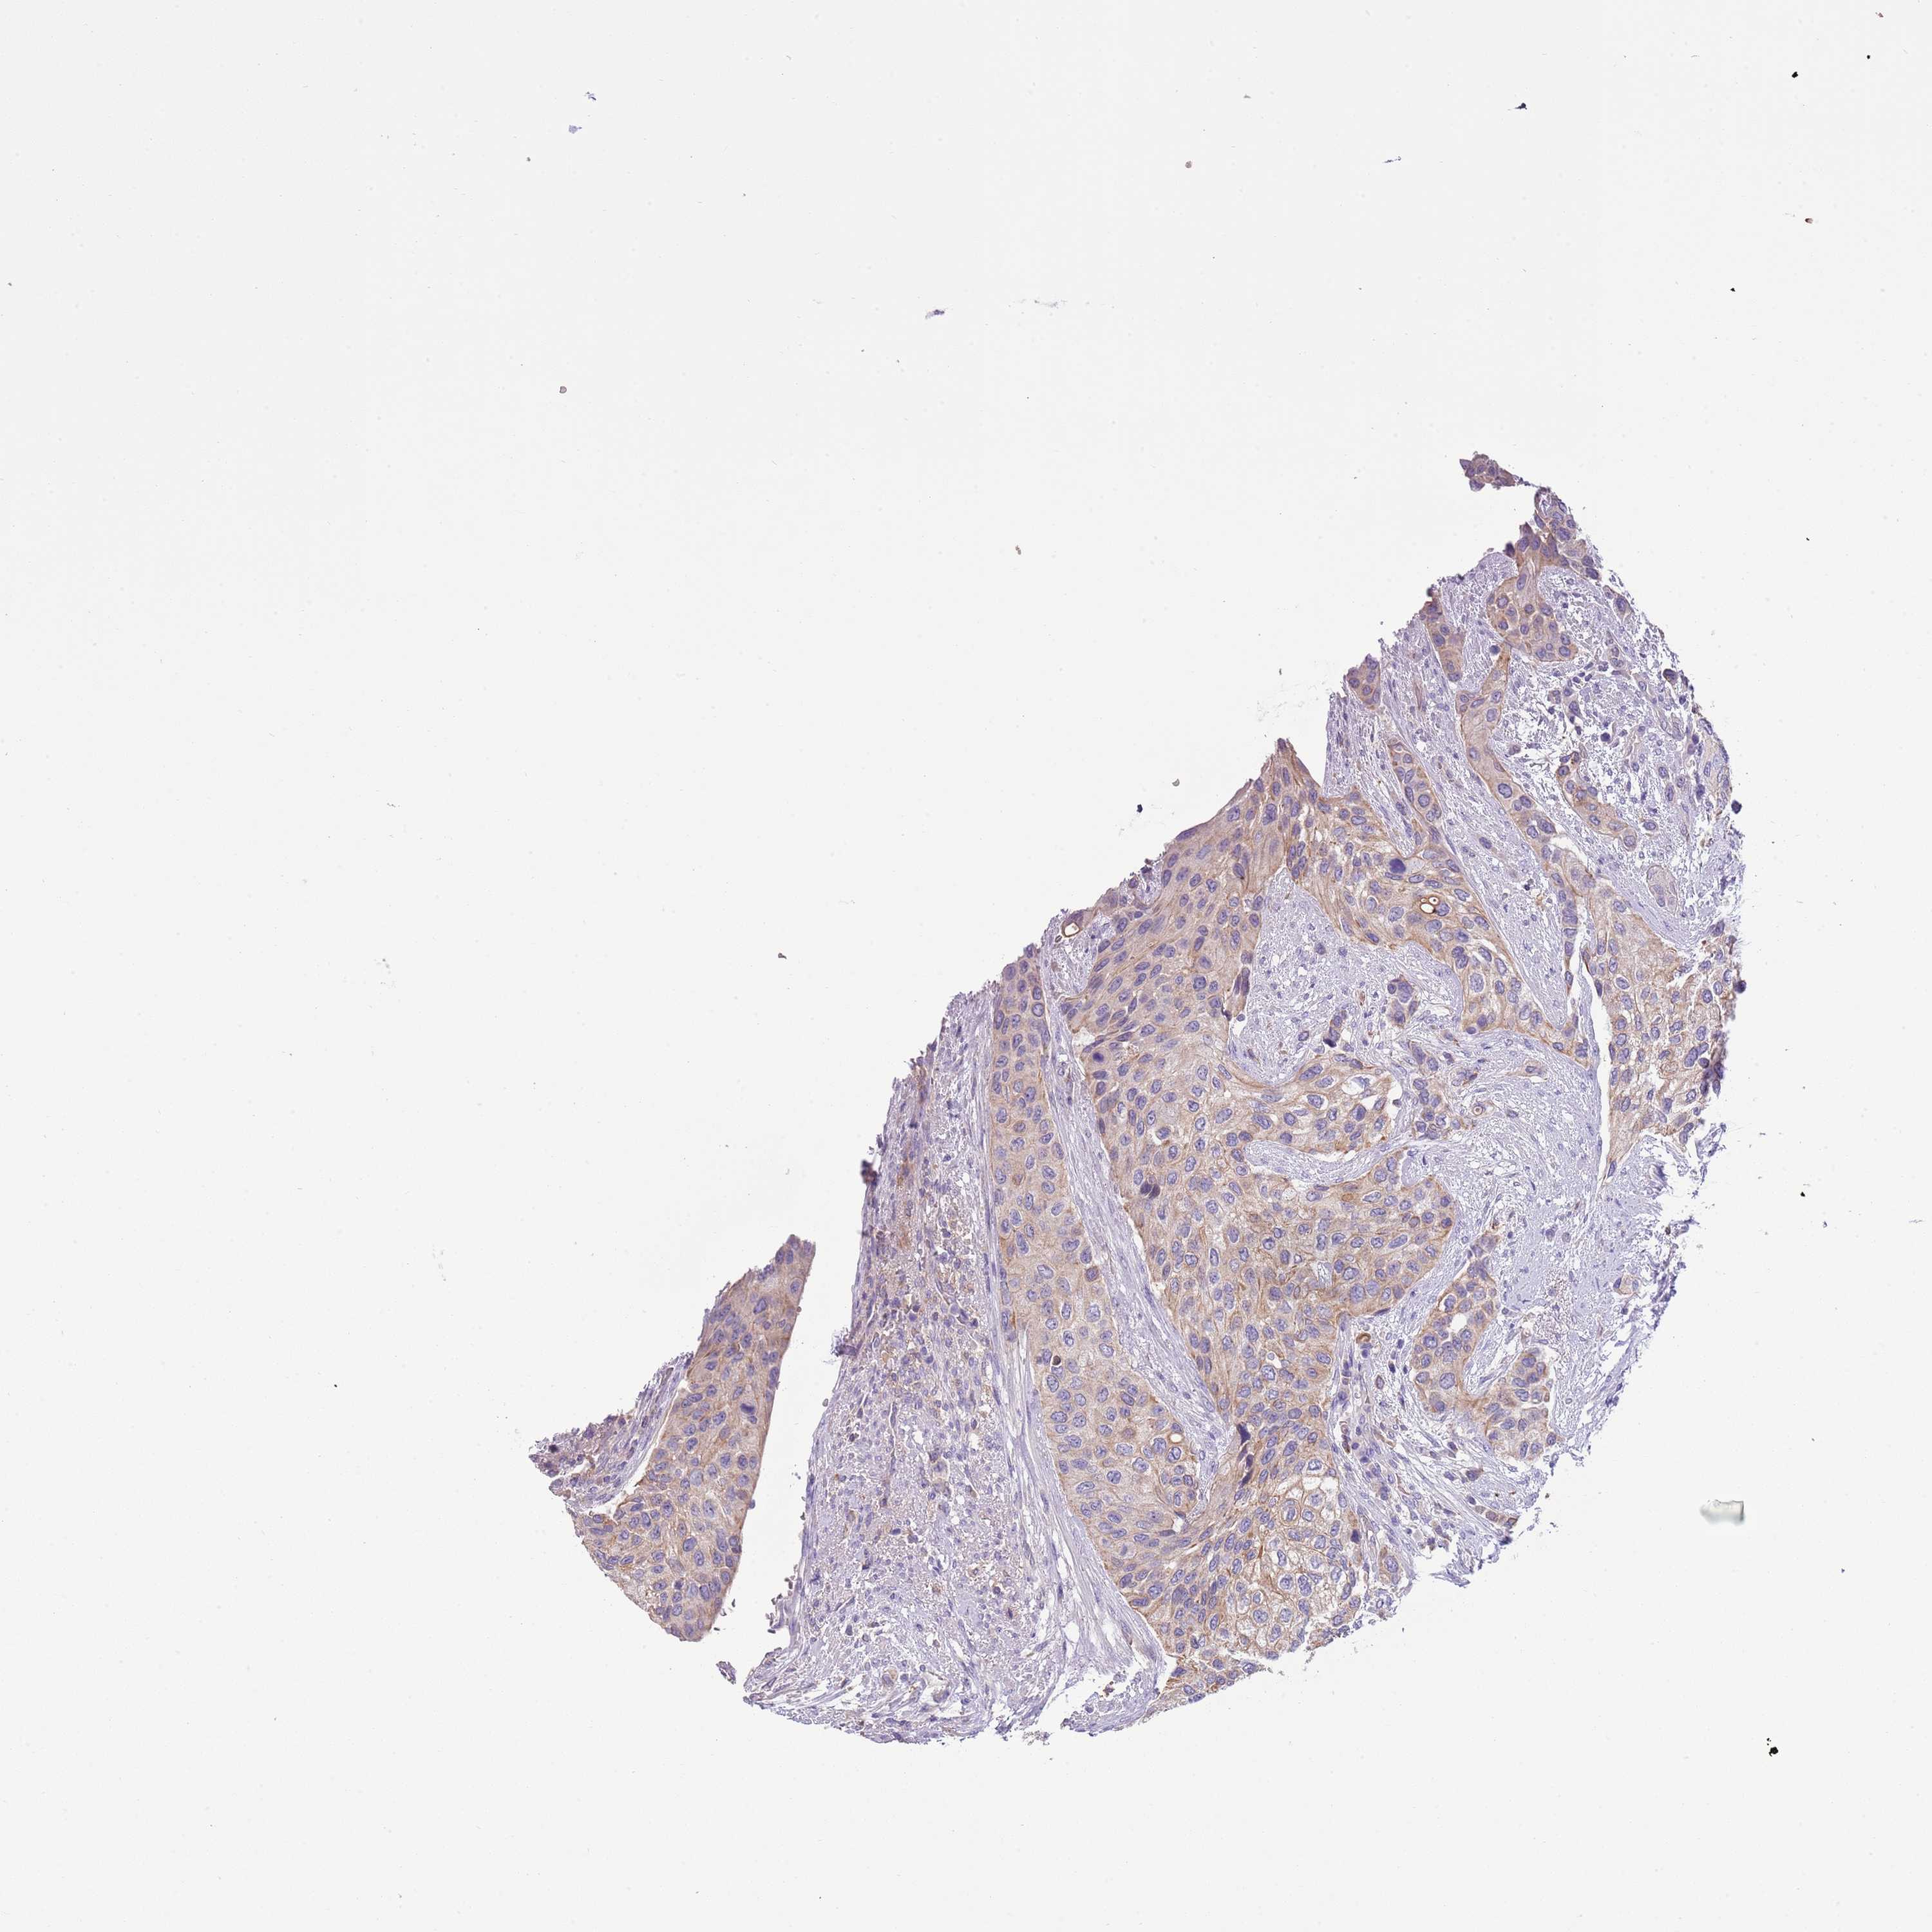

UROTHELIAL CANCER - Protein expressioni

A mouse-over function shows sample information and annotation data. Click on an image to view it in a full screen mode. Samples can be filtered based on level of antibody staining by selecting one or several of the following categories: high, medium, low and not detected. The assay and annotation is described here.

Note that samples used for immunohistochemistry by the Human Protein Atlas do not correspond to samples in the TCGA dataset.

Antibody stainingi

Antibody staining in the annotated cell types in the current human tissue is reported as not detected, low, medium, or high, based on conventional immunohistochemistry profiling in selected tissues. This score is based on the combination of the staining intensity and fraction of stained cells.

Each image is clickable and will lead to virtual microscopy that enables deeper exploration of all samples and also displays staining intensity scores, fraction scores and subcellular localization as well as patient and tissue information for each sample.

Antibody HPA047927

Staining

High

Medium

Low

Not detected

Intensity

Strong

Moderate

Weak

Negative

Quantity

>75%

75%-25%

<25%

None

Location

Nuclear

Cytoplasmic/membranous

Cytoplasmic/membranous,nuclear

Urothelial carcinoma, High grade

Urothelial carcinoma, Low grade

Urothelial carcinoma, NOS